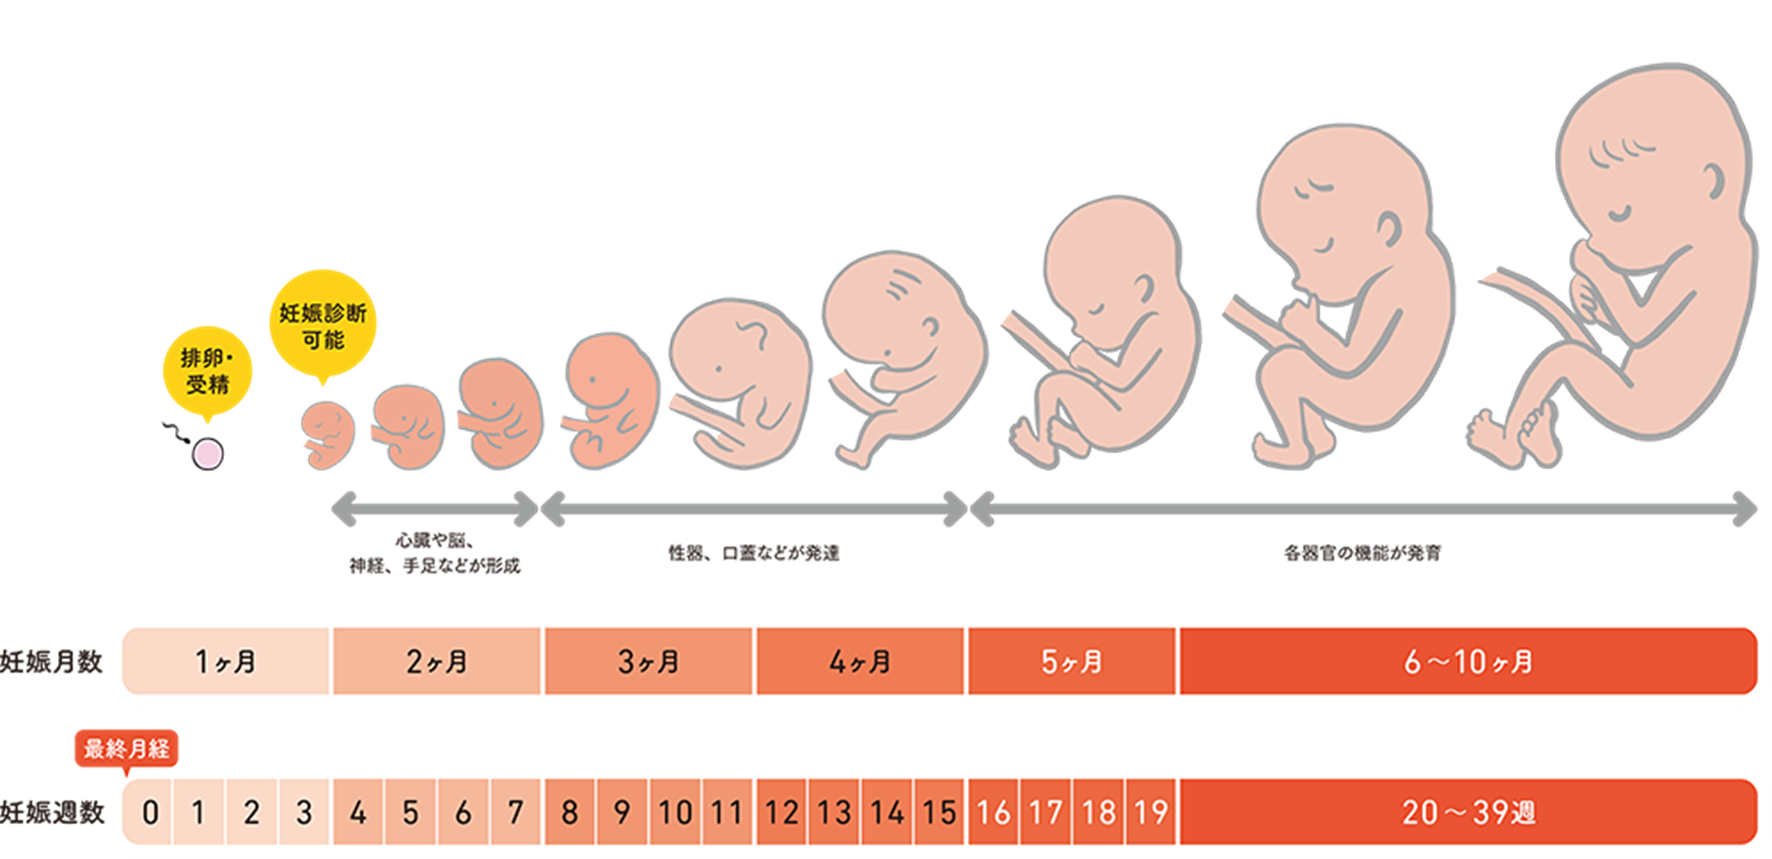

胎児は 5 週目あたりから脳の発達のプロセスを開始しますが、本当の楽しみが始まるのは、神経管が閉じて脳が 3 つの部分に分離する 6 週目か 7 週目になってからです。

生後 5 週目ごろ、赤ちゃんの脳、脊髄、心臓が発達し始めます。赤ちゃんの脳は中枢神経系の一部であり、脊髄もそこにあります。赤ちゃんの脳には考慮すべき重要な要素が 3 つあります。これらには次のものが含まれます。

ゲイザー氏によれば、4週間以内に神経板として知られる基本的な構造が発達し、これが神経系の前駆体であると考えられているという。 「このプレートは伸びて折り重なって神経管を形成します。神経管の頭側部分は脳になり、尾側部分は伸びて最終的には脊髄になります」と彼女は説明する。

神経管は成長を続けるが、6週目か7週目あたりで神経管が閉じ、頭側部分(原始脳とも呼ばれる)が前脳、中脳、後脳という3つの異なる部分に分離するとゲイザー氏は言う。

ゲイザー氏は、妊娠第 2 期になると、脳が体の機能を制御し始めると述べています。これには、後脳、より具体的には小脳に由来する特定の動きが含まれます。

最初の顕著な発達の 1 つである吸啜と嚥下は、生後 16 週頃に検出できます。 21週目に早送りすると、ゲイザー氏は、赤ちゃんは羊水を飲み込むことができると述べています。

発達中の中枢神経系の指示に従って呼吸運動が始まるのも妊娠第 2 学期です。脳(より具体的には脳幹)が横隔膜と胸筋を収縮させるよう指示しているため、専門家はこれを「呼吸の練習」と呼んでいます。

ゲイザー博士は、胎児は妊娠第 2 学期後半に聴覚を持ち始め、発達中の視床下部からの脳波がより成熟するにつれて睡眠パターンが現れると指摘しています。

ゲイザー教授によると、妊娠第 2 学期の終わりまでに、胎児の脳は構造的には成人の脳とよく似ており、脳幹がほぼ完全に発達しているという。

妊娠後期には何が発達するのでしょうか?

第三学期は急速な成長に満ちています。実際、赤ちゃんが成長し続けるにつれて、脳も成長します。 「脳の複雑な表面がすべて現実化し、半分(右脳と左脳)が分離します」とゲイザー氏は説明します。

脳は妊娠第 1 学期の早い時期に形成され始め、出産まで続きます。妊娠中、胎児の脳の発達は、呼吸、蹴り、心拍などの特定の動作を担当します。